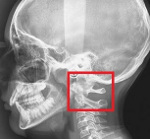

Наряду с клиническим обследованием важное значение в диагностике имеет выполнение рентгенографии черепа и рентгенографии шейного отдела позвоночника. С целью визуализации мягкотканных структур краниовертебрального перехода назначают МРТ головного мозга и МРТ позвоночника в шейном отделе. Исследование выполняется в режимах Т1 и Т2, в сагитальной и аксиальной проекциях. По показаниям проводят МРТ сосудов головного мозга. При невозможности МРТ-обследования, а также для более точной визуализации костных образований краниовертебральной зоны, выполняют КТ позвоночника и КТ головного мозга.